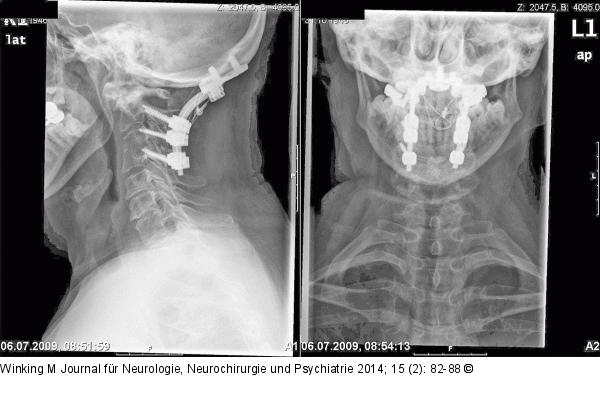

Abbildung 8: Rheumatische Wirbelsäule Röntgenaufnahmen nach okzipito-zervikaler Stabilisierung durch ein Schrauben-Stab-System und Beckenkammspaninterposition mit Titan-Kabelcerclage gesichert. |

Röntgenaufnahmen nach okzipito-zervikaler Stabilisierung durch ein Schrauben-Stab-System und Beckenkammspaninterposition mit Titan-Kabelcerclage gesichert. |